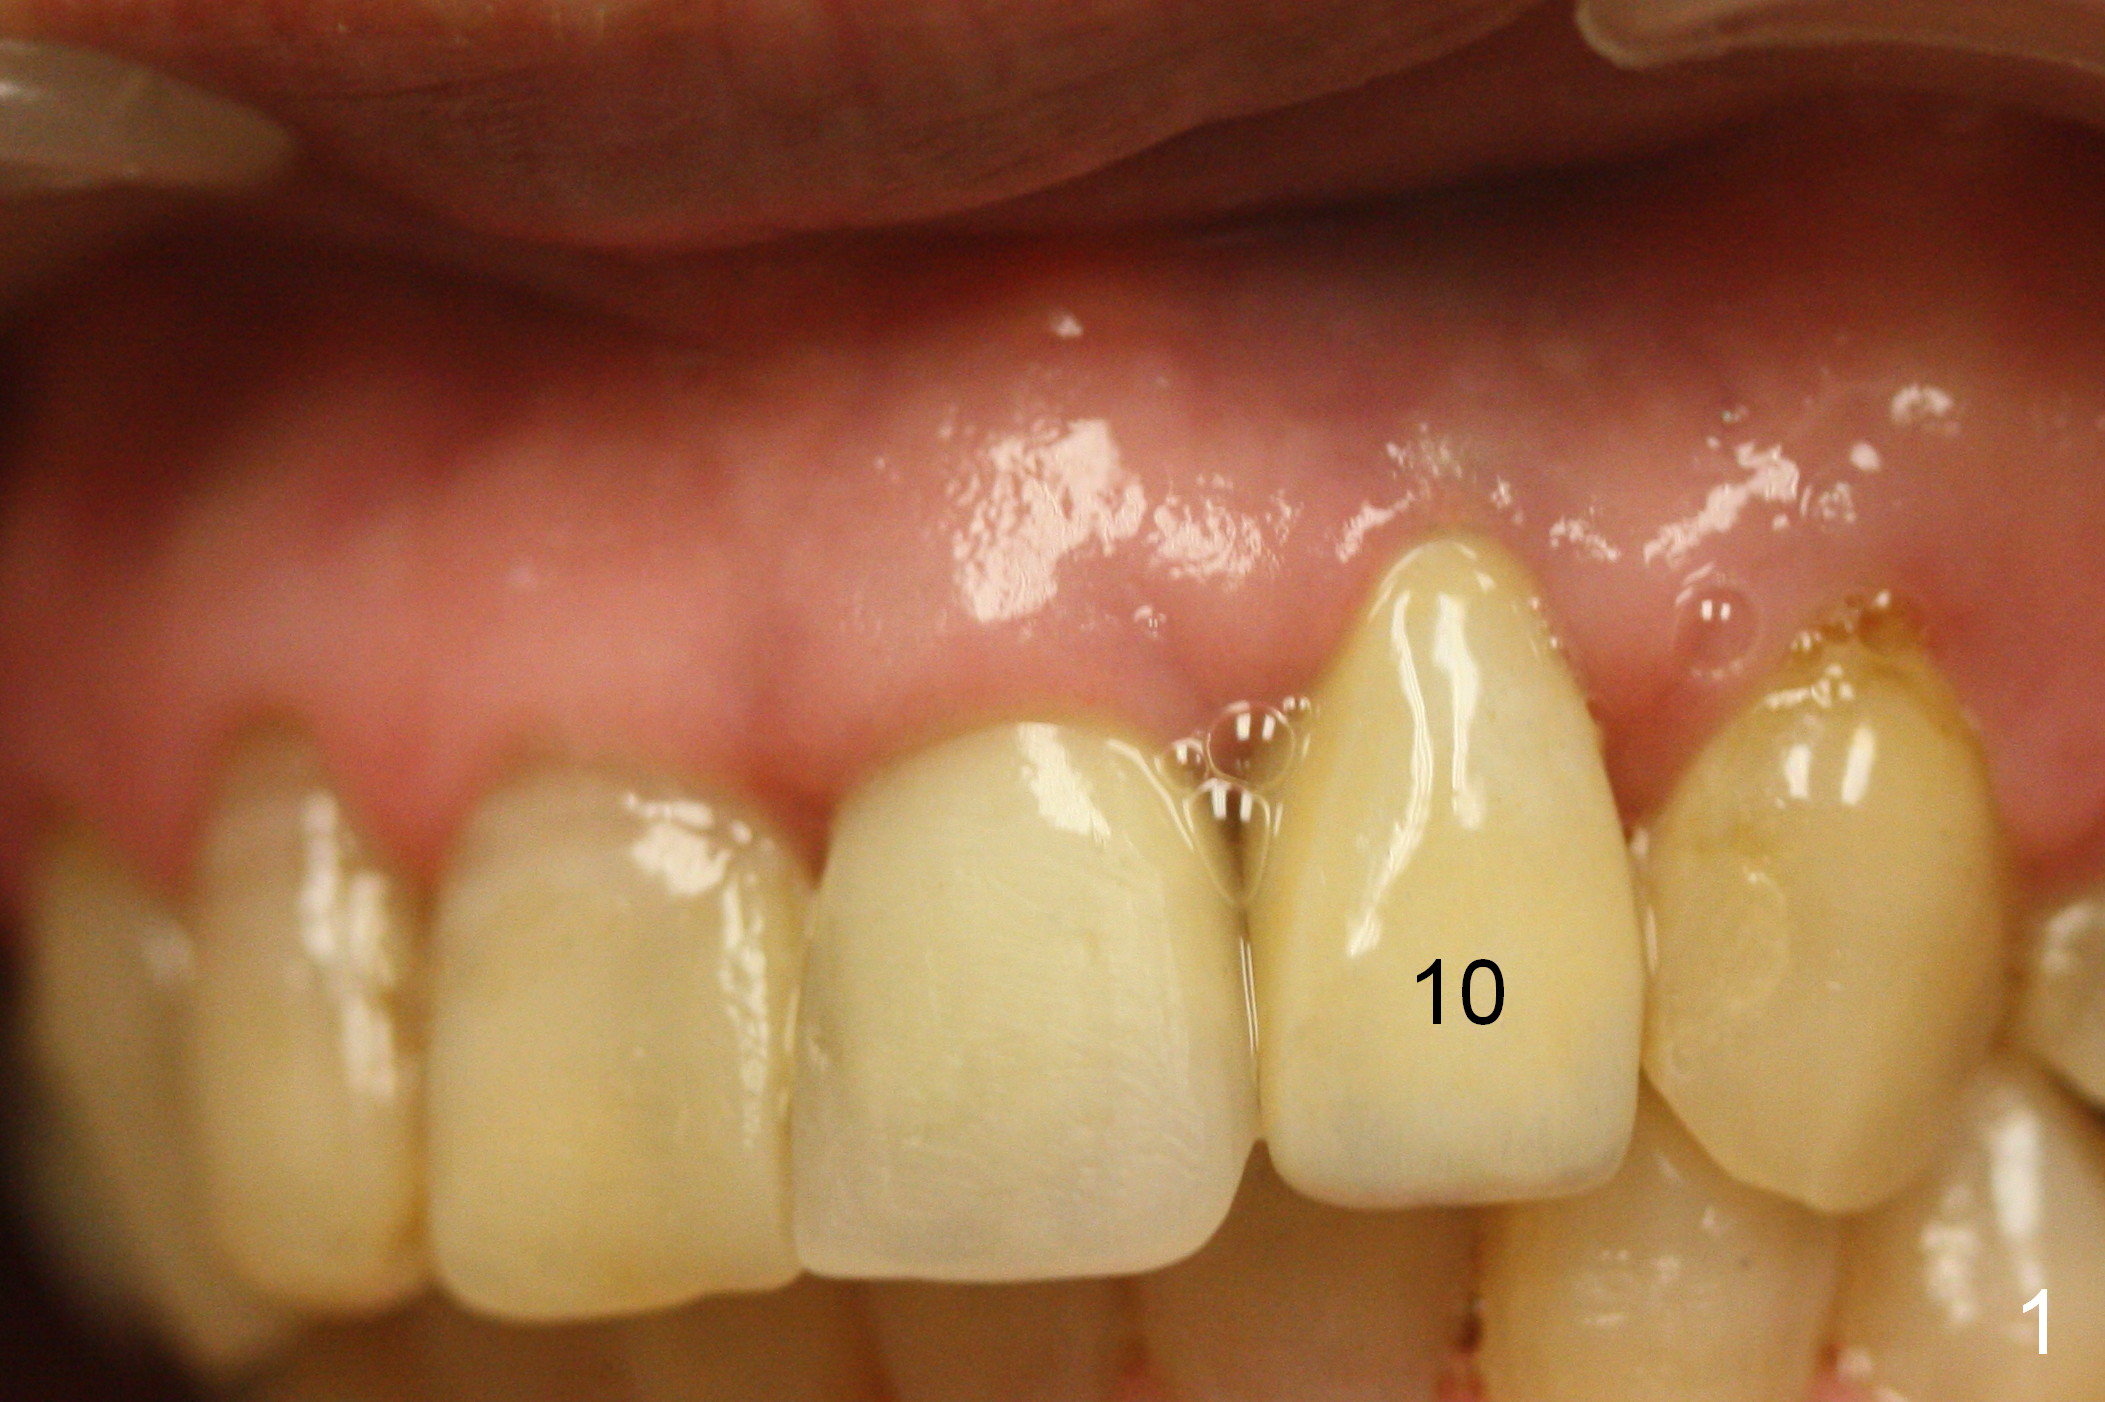

The 57-year-old lady does not like the crown at the site of #10 immediately when it is cemented (Fig.1). When the upper lip is retracted, it appears that the implant is immediately underneath the gingiva (Fig.2 *). It is slightly tender when palpated. The patient refuses CBCT. When the buccal flap is raised, the implant is found to be exposed buccally (Fig.3). When it is removed, the coronal portion of the palatal wall is thin (Fig.4). It appears that there is bone in the mid and apical thirds of the palatal wall, where an osteotomy is initiated using a 1.2 mm pilot drill. When the latter reaches 18 mm from the crest, the nasal floor appears to be perforated. The latter is confirmed by PA (Fig.5). As the osteotomy are increasing in diameter, force is applied as palatally as possible without perforating the palatal wall too much. When a 3.5x20 mm implant is placed (30 Ncm), it is palatal to the labial wall. The defect is filled by allograft and Osteogen, covered by long termed resorption membrane. The buccal flap is sutured (Fig.7). A proposal to place gingival graft is rejected. The implant is shown to have been positioned more or less normally (Fig.8). A removable temporary appliance is fabricated. Periodontal dressing is applied.

As expected, there is midbuccal tissue deficiency (Fig.9,10: 2 months postop). After discussion, a free gingival graft from the palate is placed (Fig.11,12 *). Two weeks later, the graft sloughs (Fig.13). A pedicled flap is designed (Fig.14) and transferred to repair the defect (Fig.15,16).